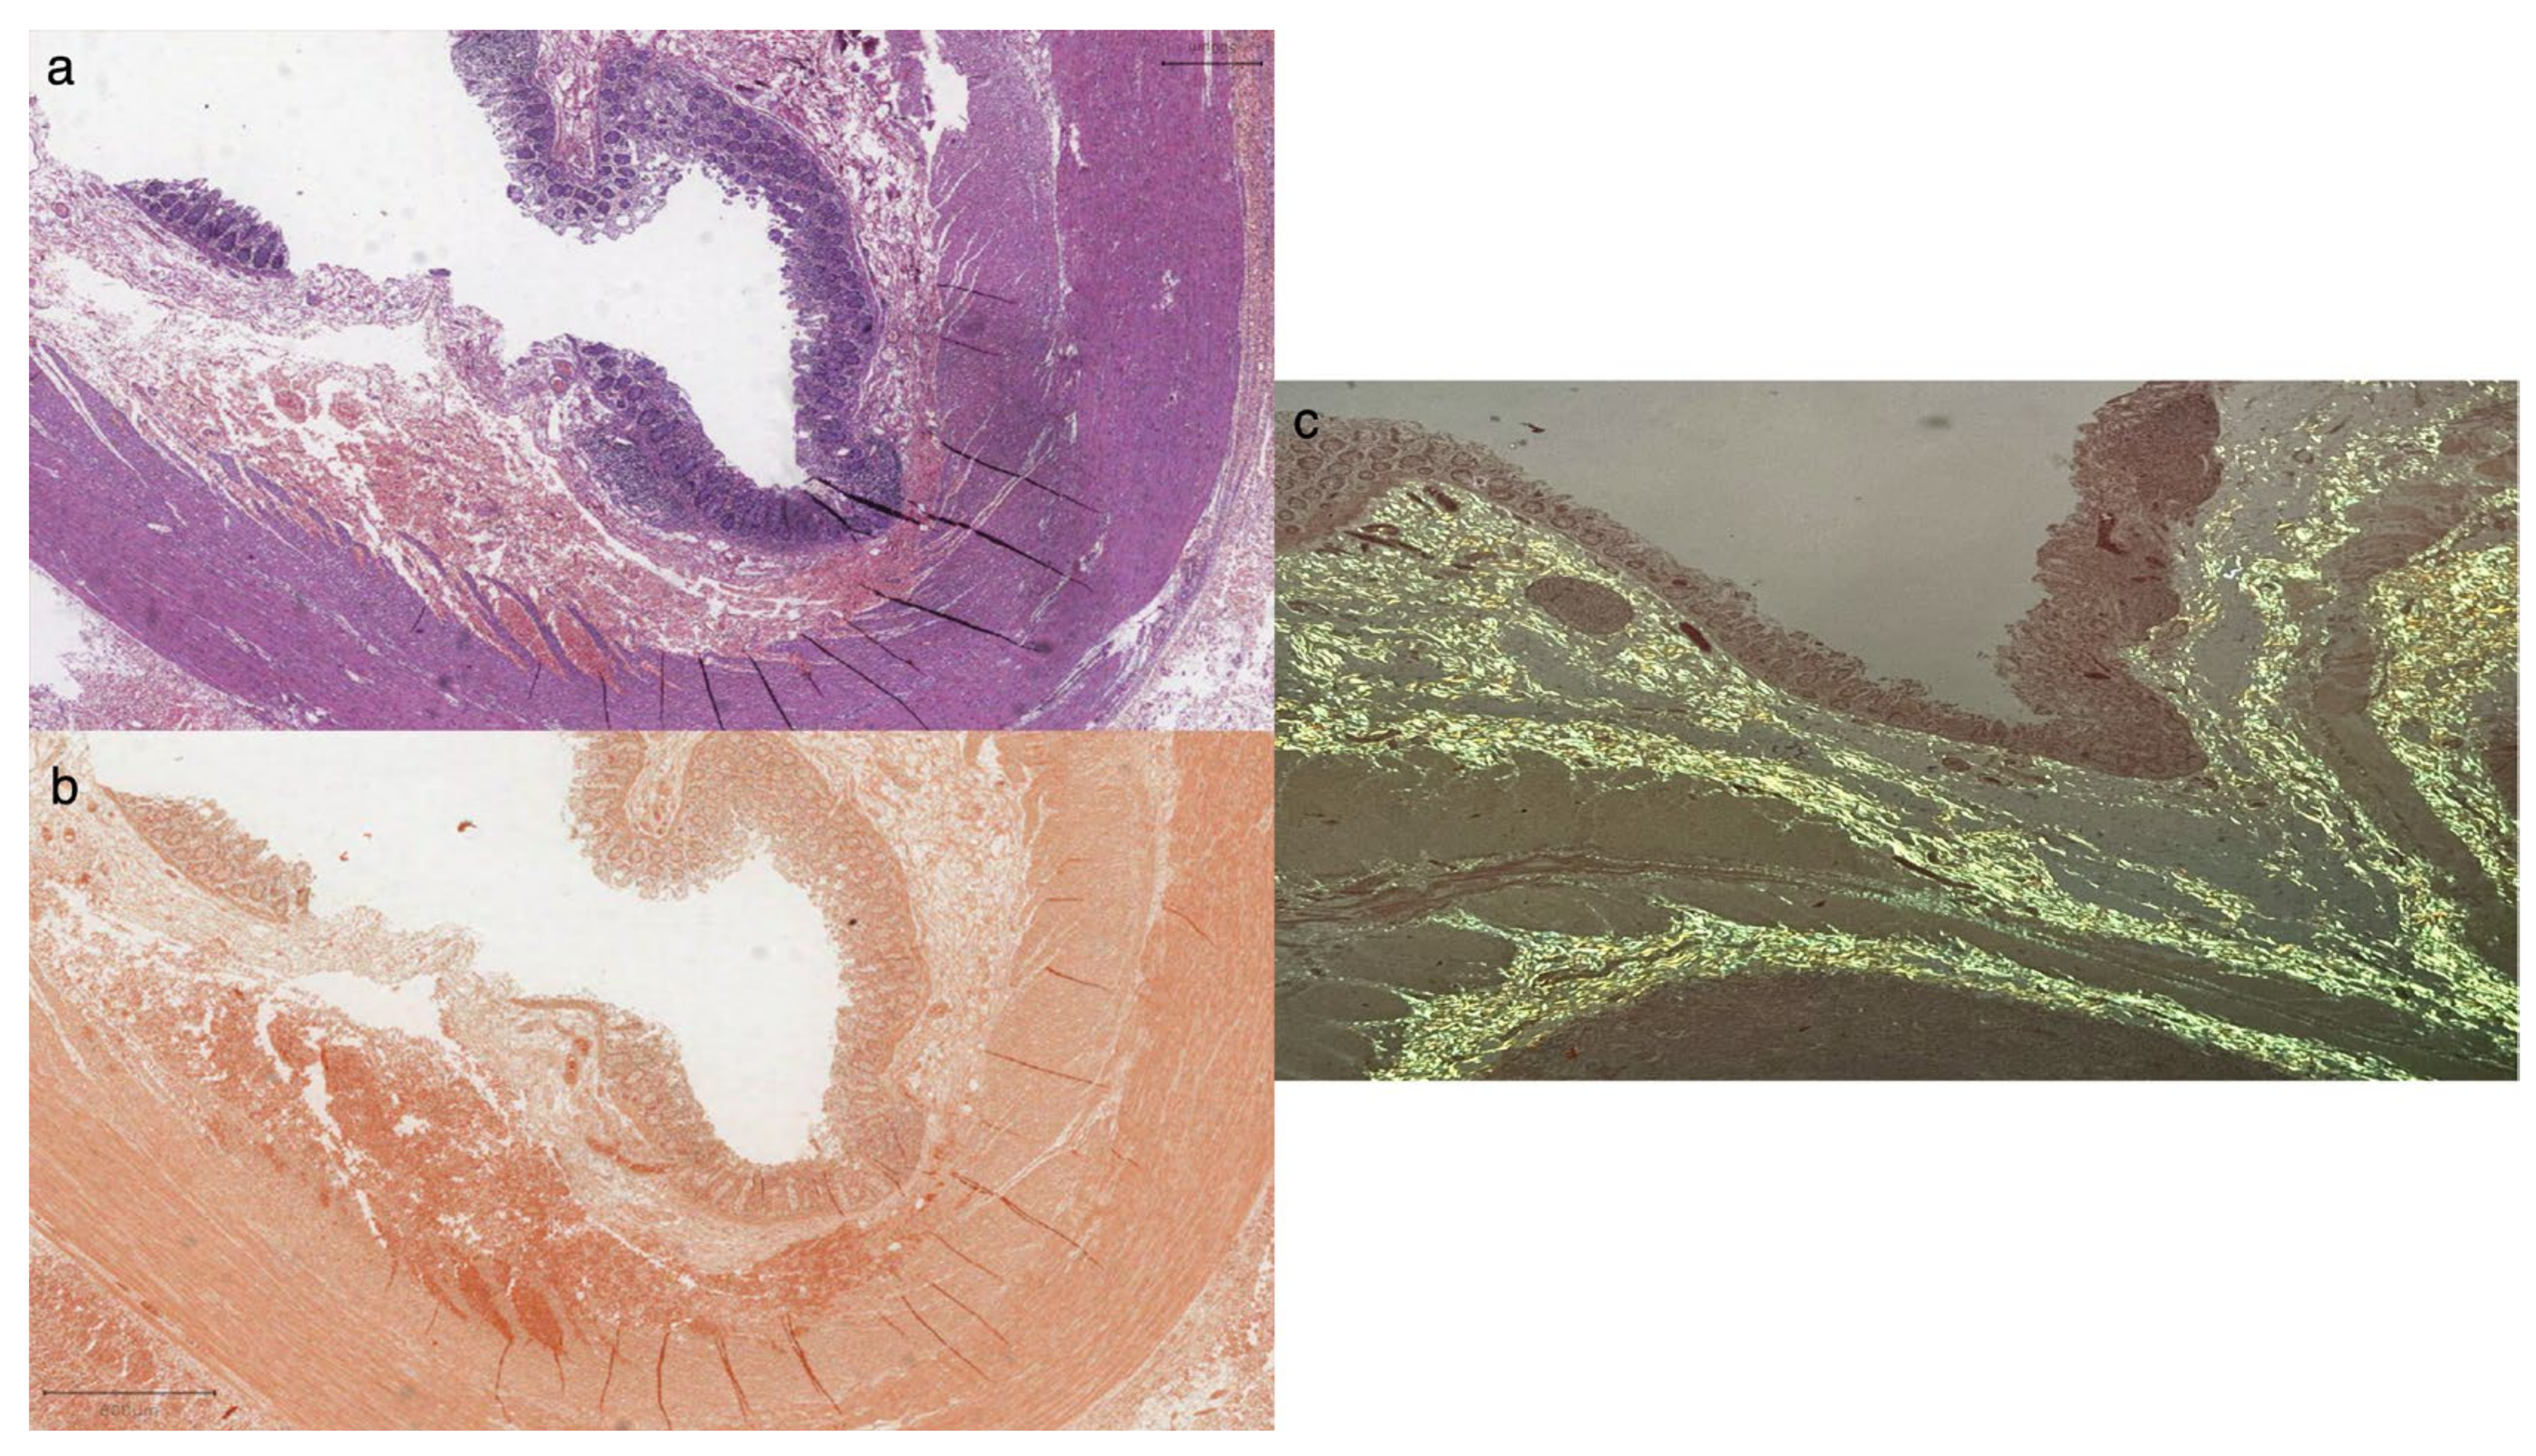

Scattered polytypic plasma cells (CD138+), rare CD30+/EBER-activated blasts, and occasional CD117+ mast cells were also observed. Histological staining with Congo Red revealed widespread amyloid deposits with intense apple-green birefringence on polarized observation (Figure 3). No signs of ganglionic hyperplasia were seen.

Figure 3.

Histologic examination (a) revealed large intestine mucosal atrophy harboring amorphous material in the submucosa and muscularis propria (H&E stain), staining intensely for Congo Red along submucosal and muscular layers (b); observation under a polarized microscope showed apple-green (c) birefringence suggestive of amyloid deposits. Scalebar = 800 microns.